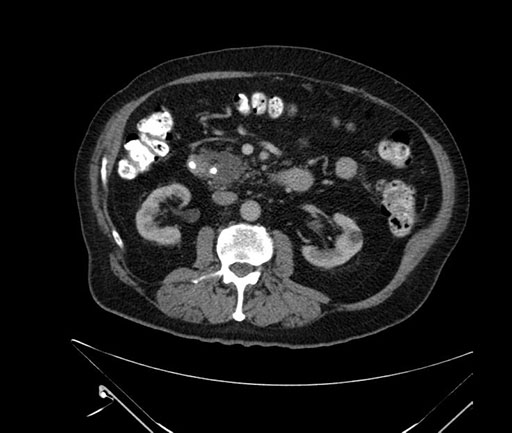

Imaging Analysis

Look through the patient's CT scan to identify any areas of concern for the necessary procedure.

Based on your CT findings, which issue(s) would give reason for "planned slowing down moment(s)" in this case?